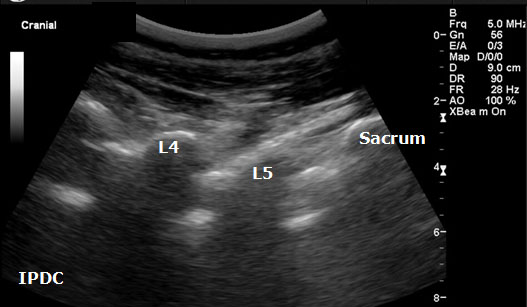

Sonoanatomy

A low-frequency curved array transducer is needed in the lumbar spine region. The 2 views used to visualize the spinal canal and its associated landmarks include the paramedian longitudinal (Figure 14) and transverse (axial) windows (Figure 15). A paramedian longitudinal (sagittal) view is the best window for sagittal scanning that minimizes the acoustic artifact shadowing associated with bony structures.[40][43] The appropriate interspace can be identified in the sagittal view based on counting from the landmark of the sacrum.

In the transverse approach the transducer is placed perpendicular to the long axis of the spine. The window is identified in which shadow of the spinous processes is minimal. Structures that can be visualized with ultrasound include the ligamentum flavum/posterior dura complex, spinous processes, transverse processes, superior articular processes, facet joints, and the posterior border of the vertebral body. In certain cases it is not always possible to distinguish the ligamentum flavum from the posterior dura and the anterior dura from the posterior longitudinal ligament and the vertebral body. Ultrasound has also been utilized as an adjuvant tool in the performance of caudal epidurals (Figure 16).